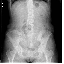

椎体骨折(10.69MB)

椎体骨折2(10.61MB)

腰椎骨折伴截瘫(10.49MB)

椎体骨折

椎体骨折2

腰椎骨折伴截瘫